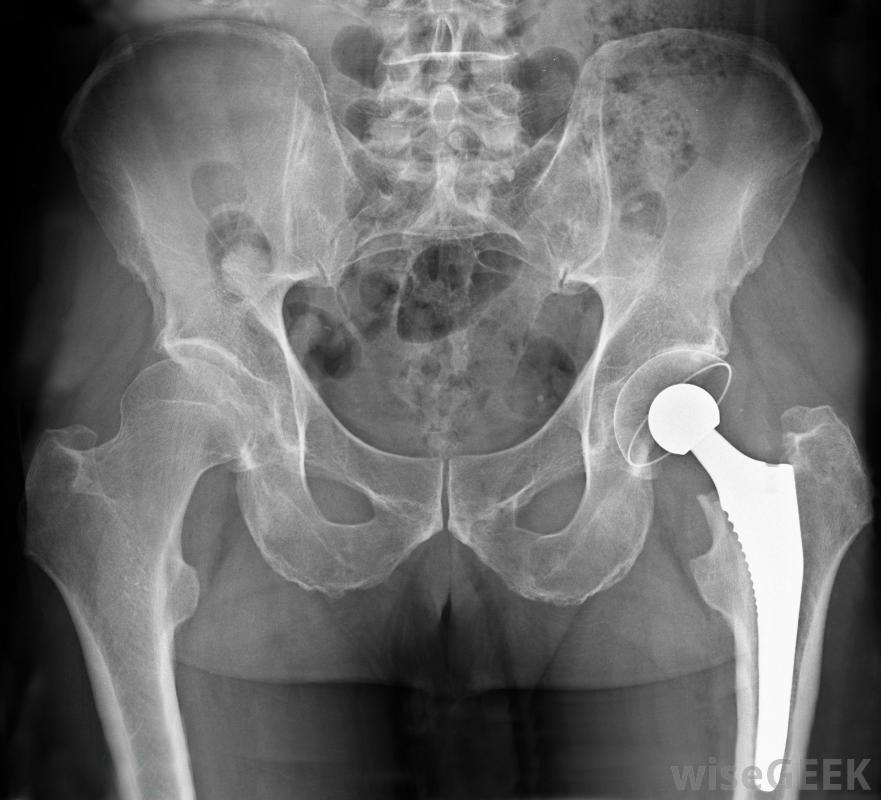

選擇性手術是計劃好的非急診手術,允許病人和醫生決定手術的最佳時間和地點。從髖關節置換到鼻整形,有很多手術可以被認為是選擇性的,大多數醫院都提供選擇性手術。主要優點是選擇性手術的特點是,由于排除了各種各樣的機會和緊急情況,因此它有一個更加可控和可預測的結果。病人在擇期手術前接受吸入麻醉有些選擇性手術在醫學上是必要的,但不是緊急的。這類手術通常在手術前與醫生詳細討論,病人可以尋求第二意見,并與其他外科醫生預約,以找到最適合他或她的需要的外科醫生。切除乳房腫塊切除術是醫學上必要的緊急手術的一個例子髖關節置換手術有時是一種選擇性手術,其他選擇性手術本質上被認為是美容手術,這意味著它們沒有直接的醫學價值,但是對病人來說,它們可能對自尊和社會地位非常有益例如,去除面部葡萄酒色斑的手術是一種選擇性的整容手術,但是去除葡萄酒色斑會對患者的生活產生很大的影響。選擇性手術是非緊急的,并且允許醫生和病人決定完成手術的最佳時間。有時,"選擇性手術"和"選擇性手術"的區別會被混淆,尤其是保險公司,保險公司可能會拒絕支付膝關節置換手術的費用,理由是即使患者的生活質量會大大降低,患者也不會因此而死亡,醫生可能會辯稱手術在醫學上是必要的這可能會導致病人和他們的保險公司之間的爭斗,試圖獲得一個選擇性的程序覆蓋,在接受擇期手術前,最好先向保險公司了解一下手術的情況。盡管擇期手術是在非緊急情況下進行的,但這樣可以更好地控制手術,這仍然是危險的,病人有麻醉不良反應、感染和各種手術并發癥的風險,這些都應該在手術前討論通常情況下,外科醫生喜歡在手術前進行測試并與患者會面,以確認患者是手術的合適人選,患者將被要求遵循售后服務說明并參加后續預約,以監控手術的成功準備接受整容手術(一種選擇性手術)的女性。